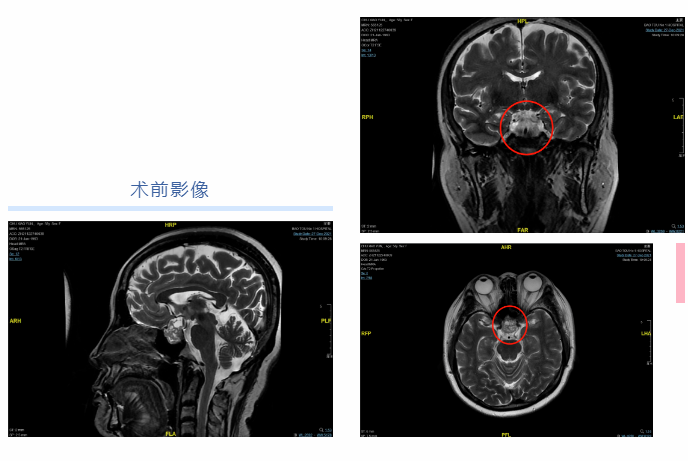

今年58岁的褚大妈,自2年前起就感觉看东西模糊不清,却没有理会。一个月前她感觉视物不清的症状逐渐加重,甚至迎面走来的熟人都不能辨认,且出现了头闷、头晕不适等症状,去附近医院检查,经诊断确诊为垂体瘤。

为求进一步治疗,褚大妈来到包医一附院神经外科。神经外科神经内镜组文平、杨建华、白宇医师共同为褚大妈进行了神经内镜下经鼻蝶骨垂体瘤切除的手术治疗。